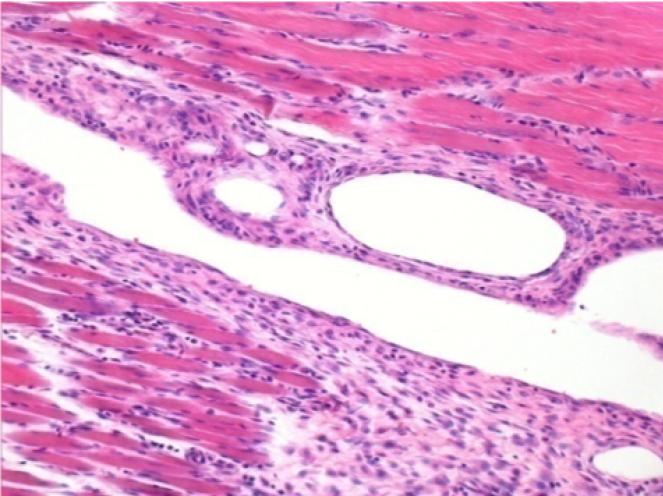

10 days after Endopeel Injection

10 days after Endopeel Injection 0.1ml in the right pretibial muscle.

Here you may see the formation of the vacuoles which are surrounded by lymphocytes. Vacuoles are different from tissue necrosis . The presence of lymphocytes is related to the permeability of the cell membranes.

L : Control-100xD10

R:100xD10

R :200xD10

R :400xD10